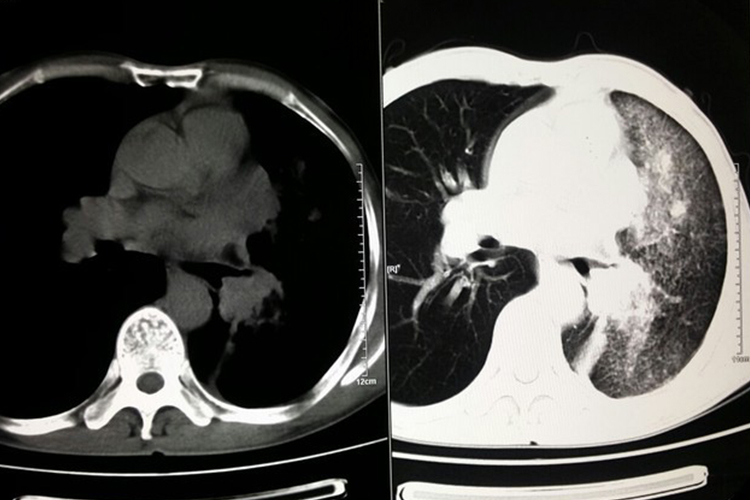

肺癌又称原发性支气管肺癌,临床常见咳嗽、血痰、胸痛、发热、气促等症状。影像学表现可分为中央型肺癌和周围型肺癌两种,具体如下:

中央型肺癌:发生在肺段和段以上支气管,表现为病变处支气管壁增厚、支气管腔狭窄;肺门出现形态不规则的软组织肿块;远端肺组织阻塞性改变,包括阻塞性肺炎、肺不张,表现为远端肺组织实变,或肺叶、肺段均匀性密度增高,伴肺纹理聚拢、体积缩小或右肺上叶不张时,下缘形成反“S”征。

周围型肺癌:发生在肺段以下支气管,表现为肺内结节或肿块;病灶形态不规则,呈分叶状(分叶征);边缘多发细短毛刺(毛刺征);偏心性空洞,或伴有壁结节;相邻胸膜凹陷,伴线形、喇叭口样索条影牵拉改变;增强扫描呈轻、中度不均匀强化。